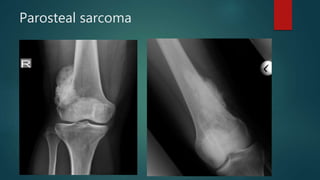

Parosteal sarcoma

• #101 There is a lobulated juxtacortical mass with dense calcification and smooth borders arising from the lateral cortex of the right femoral metaphysis measuring approximately 5.8 x 3.3 x 9.3 cm. There is no aggressive periosteal reaction. Superiorly, a thin radiolucent line separates the tumour from the cortex.  Ill-defined calcified/ossified mass arising from the lateral aspect of distal femu